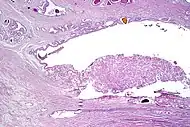

Intraductal carcinoma

Intraductal carcinoma of the prostate gland (IDCP), which is now categorised as a distinct entity by WHO 2016, includes two biologically distinct diseases. IDCP associated with invasive carcinoma (IDCP-inv) generally represents a growth pattern of invasive prostatic adenocarcinoma while the rarely encountered pure IDCP is a precursor of prostate cancer.[19] The diagnostic criterion of nuclear size at least 6 times normal is ambiguous as size could refer to either nuclear area or diameter. If area, then this criterion could be re-defined as nuclear diameter at least three times normal as it is difficult to visually compare area of nuclei.[19] It is also unclear whether IDCP could also include tumors with ductal morphology.[19] There is no consensus whether pure IDCP in needle biopsies should be managed with re-biopsy or radical therapy. A pragmatic approach would be to recommend radical therapy only for extensive pure IDCP that is morphologically unequivocal for high-grade prostate cancer.[19] Active surveillance is not appropriate when low-grade invasive cancer is associated with IDCP, as such patients usually have unsampled high-grade prostatic adenocarcinoma.[19] It is generally recommended that IDCP component of IDCP-inv should be included in tumor extent but not grade.[19] However, there are good arguments in favor of grading IDCP associated with invasive cancer.[19] WHO 2016 recommends that IDCP should not be graded, but it is unclear whether this applies to both pure IDCP and IDCP-inv.[19]

Intraductal carcinoma of the prostate with an infiltrative growth pattern may be morphologically difficult to distinguish from invasive cancer. One focus shows comedonecrosis (arrow), morphologically suggesting Gleason pattern 5 invasive carcinoma (a haematoxylin and eosin, b CK5/6)[19]

Intraductal carcinoma of the prostate with very patchy basal cells identified by immunohistochemistry. At least some of the glands lacking basal cell immunoreactivity represent intraductal rather than invasive carcinoma (a haematoxylin and eosin, b CK 5/6)[19]

Ductal adenocarcinoma may have a prominent cribriforming architecture, with glands appearing relatively round, and may thereby mimic intraductal adenocarcinoma, but can be distinguished by the following features:[10]